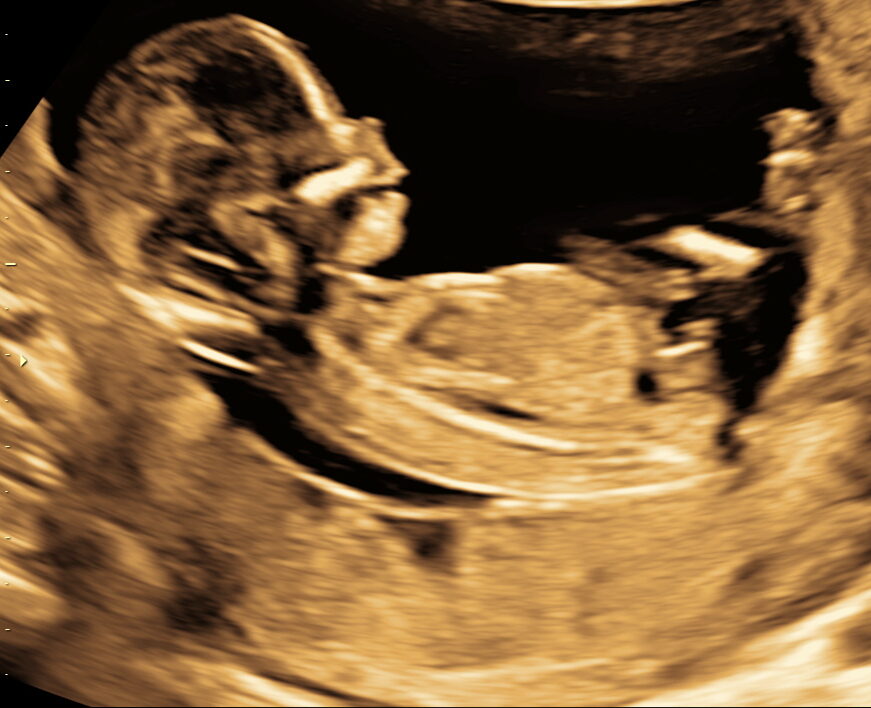

3d/4d Scanning

Udføres fra uge 27+0 – 32+0

Denne type scanning kan foretages i hele graviditeten, dog opnås det bedste resultat mellem graviditetsuge 27+0 til og med 32+0, hvor barnets alder og mængden af fostervand giver de mest optimale betingelser for billedkvaliteten.

Her træder portrættet virkelig frem da vi kan scanne hele vejen rundt om fosteret. Man ser måske et træk man kan genkende fra far eller mor?

4D er små filmklip mellem 5-10 sekunder hvor man kan se fosterets bevægelser og grimasser. Man kan også være heldig at se den lille drikke fostervand eller åbne sine øjne.

Er der forhold til stede der vanskeliggøre udførslen af scanningen, tilbydes i en ny tid uden beregning frem til graviditetsuge 32+0.

De helt perfekte billeder afhænger dog også af forhold, som vi ikke altid kan ændre på og det må forventes, at billedernes kvalitet er forskellige gravide imellem.